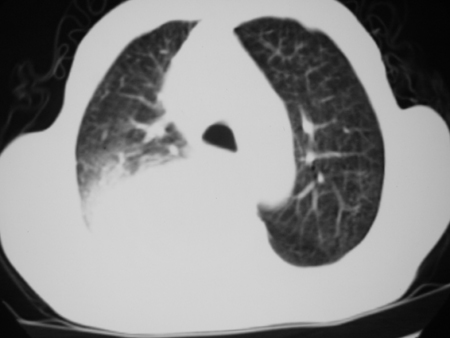

标题: CT24778:肺部病变

男77岁,胸痛就诊

右侧胸腔积液,部分包裹,右下肺膨胀不全,右下肺感染。

考虑右肺门占位并下叶不张 右胸包裹积液

右肺中叶及下叶炎症并胸腔积液(部分包裹),建议抽液后复查ct除外占位。